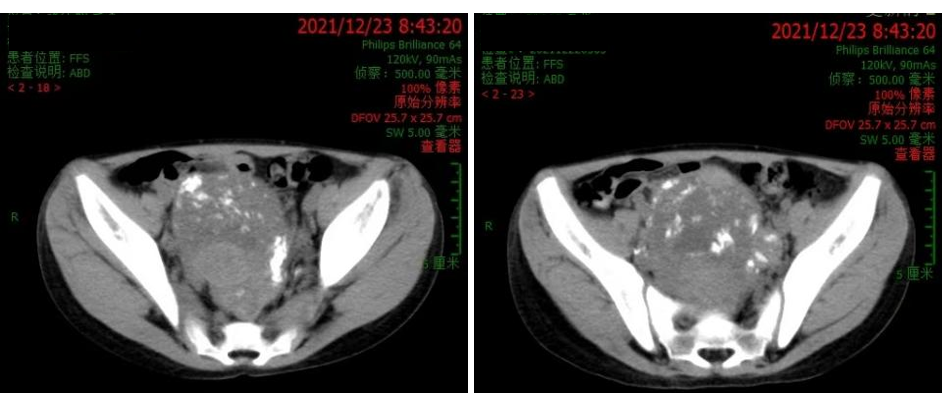

2021.12.23 腹部CT:瘤灶进一步缩小(约90.2mm×75.8mm×168mm)。

2021.12.28 行“腹膜后神经母细胞瘤切除术”,术中完整切除肿瘤。术后病理:神经母细胞瘤,分化型。术后腹部B超未见明显占位性病变,双肾轻度积水。